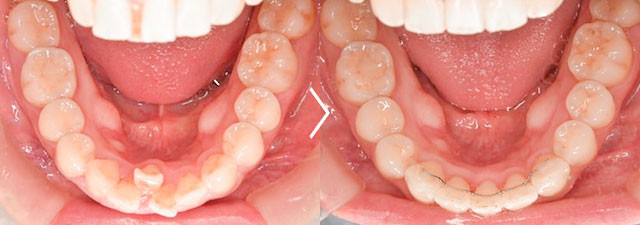

【内容】下の歯のガタつきが気になるとご来院され、1本抜歯して部分矯正を行った患者様の症例です。ワイヤー矯正で治療しました。治療期間:5ヶ月

【費用】ワイヤー部分矯正 260,000円〜(税抜)

【リスク】矯正装置が口の中に当たって口内炎が出来やすくなる方もおられます。